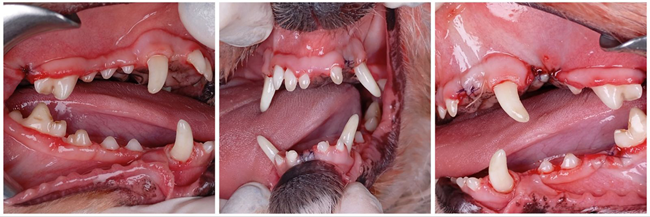

In

Figure 1.18 at right from his book,

Breed Predispositions to Dental

and Oral Disease in Dogs, Dr. Brook Niemiec

displays such a periodontal pocket at the right first molar of a

cavalier. In this case, the dog does not have evidence of gingivitis or

calculus. He points out that the lack of those signs is not unusual for

CKCSs, which warrants the need for regular cleanings despite the lack of

any clinical signs.

"You'll have another dog that comes in, say like a cavalier King Charles, has no plaque or tartar but has raging gingivitis!" (See Figure 1.18, below.)

"Cavalier King Charles Spaniels (CKCS) ... are well known for significant periodontal disease. CKCS suffer from early onset periodontal disease, especially in the maxillary premolars (as they are similar to other brachycephalic breeds). There is quite often furcation exposure of these teeth as early as two years of age. Interestingly, it is quite common for them to have advanced periodontal loss with minimal calculus and gingivitis."